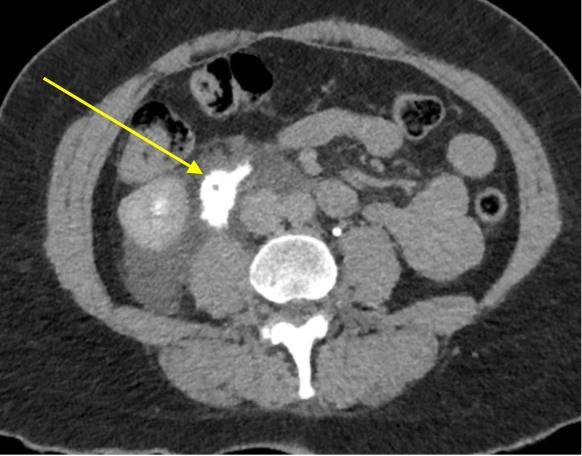

Cette image est celle d’un scanner abdominal en phase veineuse tardive, et montre une collection d’urine rétro-péritonéale (flèche). Il s’agit d’un urinome. Cette pathologie survient après une rupture urétérale, provoquant une fuite d’urine, qui se collecte et qui prend le contraste tardivement au CT.

• Le CT injecté en phase tardive (réalisé dans un deuxième temps en cas d’insuffisance rénale aiguë !) : met en évidence le signe de la toile d’araignée (visualisation des septas périrénaux) et montre une extravasion de produit de contraste sur rupture du fornix (région pyélocalicielle), de la jonction pyélo-urétérale ou de l’uretère. Il a l’avantage, par rapport à l’ultrason, de confirmer l’origine et la localisation de la brèche.